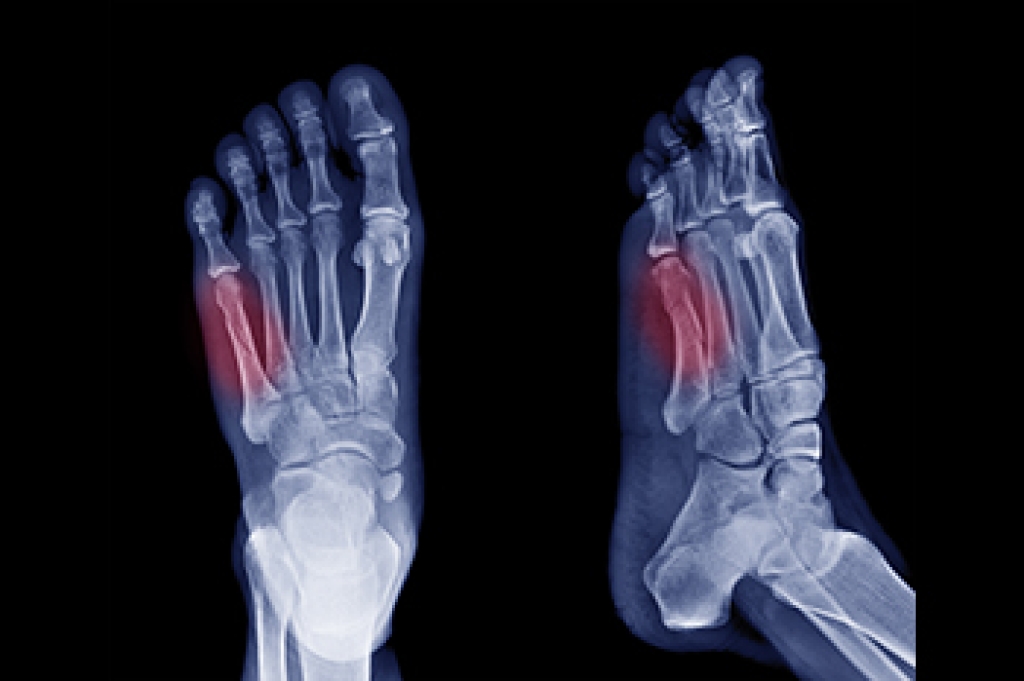

Poor blood circulation in the feet and legs is can be caused by peripheral artery disease (PAD), which is the result of a buildup of plaque in the arteries.

Plaque buildup or atherosclerosis results from excess calcium and cholesterol in the bloodstream. This can restrict the amount of blood which can flow through the arteries. Poor blood circulation in the feet and legs are sometimes caused by inflammation in the blood vessels, known as vasculitis.